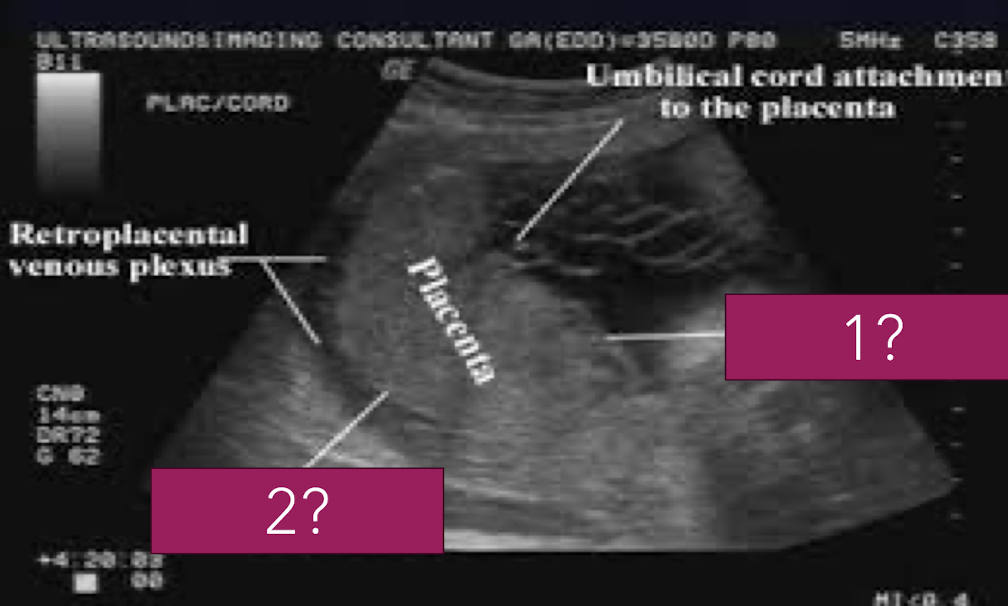

placenta anatomy

divided into 2 parts

chorionic plate (fetal surface)

surface facing amniotic fluid

continuous with chorion

basal plate (maternal surface)

surface facing uterine wall

continuous with decidua basalis

placenta plate facing amniotic fluid/fetus is called…

chorionic plate

placenta plate facing uterine wall/mom is called…

basal plate

SONO: placenta

homogeneous

pebble-gray—mildly more echogenic compared to uterine wall

may be more echogenic in 1st trimester

smooth borders

highly vascular structure

rim of myometrium outside placenta should be noted

prominent maternal vessels may be seen posterior to placenta (anechoic tubes)

placental lakes may also be seen in placenta